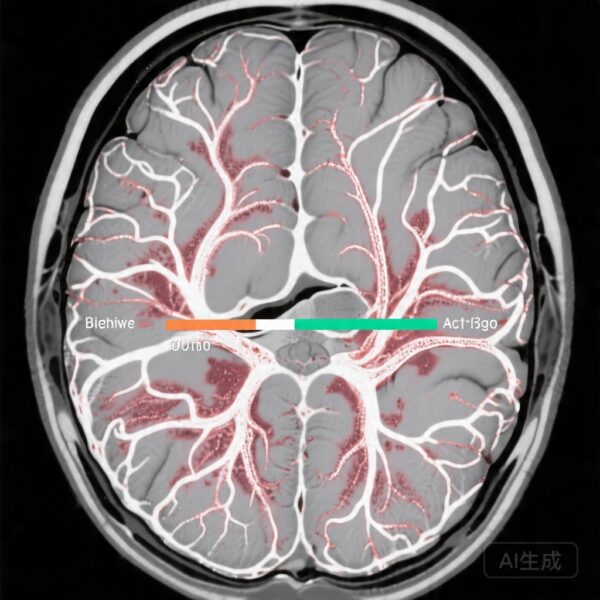

静息态功能连接

静息态fMRI分析揭示了干预期后网络整合的有意义差异。条件性神经反馈组(中风和健康对照组)表现出运动、听觉和语言网络之间的更大整合,表明支持感觉运动整合和语言处理的分布式神经系统内部通信增强。相反,非条件性中风组表现出更加混乱的连接模式,通过置换测试确认组间差异显著(P=0.01),并且连接变化具有小但有意义的效果大小(Δr=-0.1至0.1)。

这些发现与强调有效神经调节应增强任务相关网络的连贯性和功能整合而不是简单地增加区域激活的观点一致。连接变化的特异性支持了脑活动与反馈呈现之间条件关系的机制重要性。